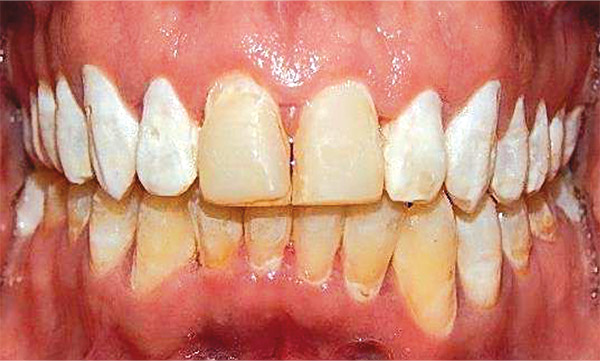

Figura 5. Frente.

En las fotografías intraorales se muestra la fluorosis dental Tf4 y Tf7, las relaciones molares clase II molar y canina bilateral (Figura 3 y 4), el apiñamiento severo superior e inferior, con el órgano dental 35 en infraoclusión. El overbite aumentado y las líneas medias dentales no son coincidentes (Figura 5), las formas de arco superior e inferior son cuadradas (Figura 6 y 7).